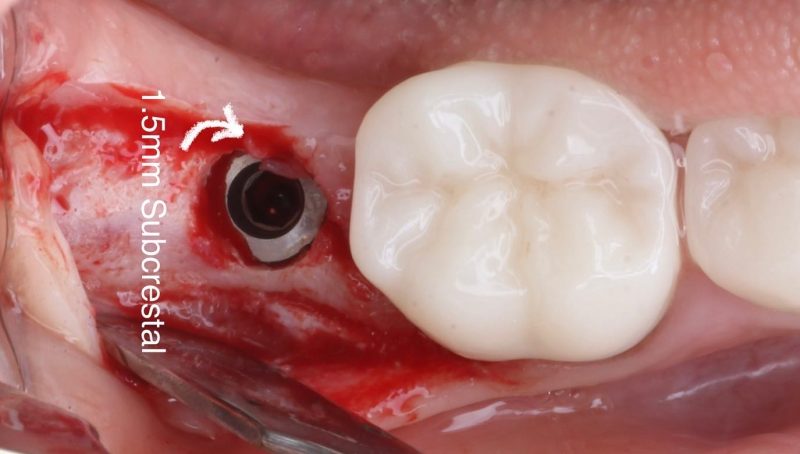

When dealing with these cases, I intentionally make my incision more lingual to preserve as much tissue as possible for the buccal side. I place the implant 1.5mm subcrestal to ensure proper stability and room for bone and soft tissue regeneration. Once the implant is in place, I use a healing cap and reposition the tissue, which allows us to achieve a thick, healthy band of keratinized tissue on the buccal.